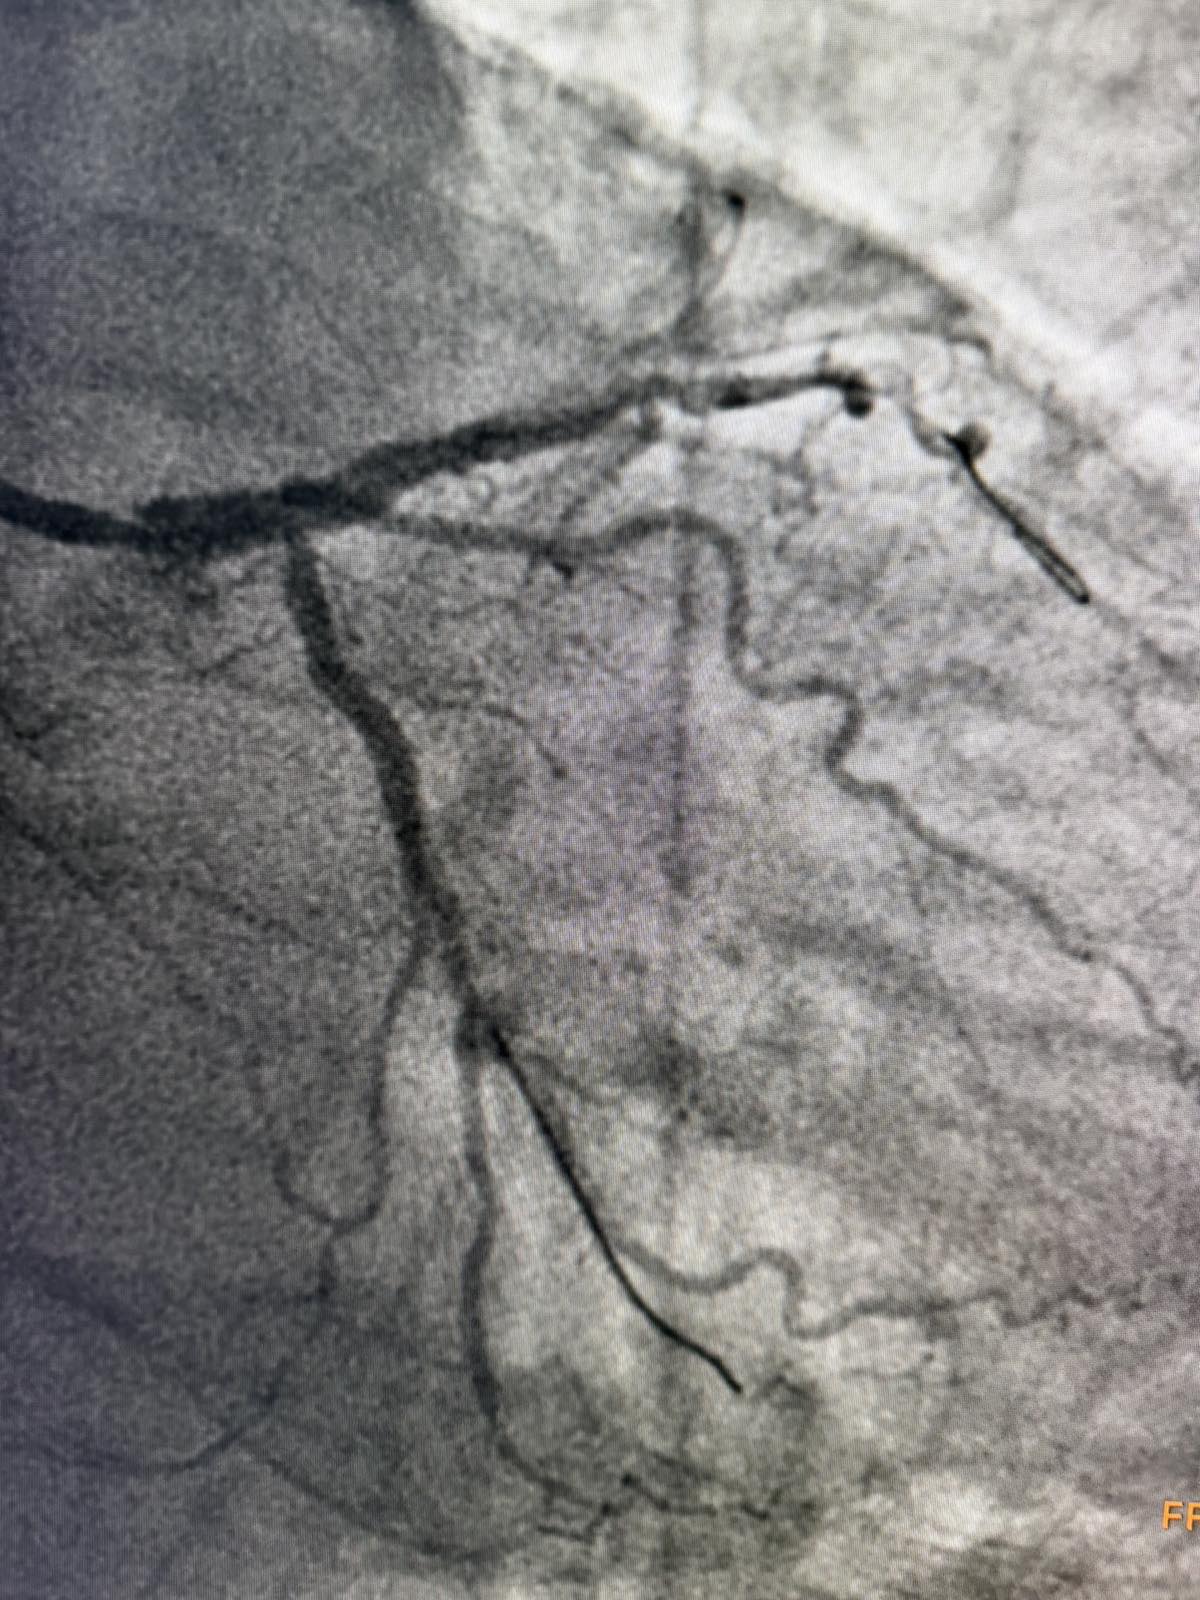

Tokom dva dana u angio sali izvedene su i izuzetno složene intervencije na koronarnim arterijama srca, uključujući perkutane intervencije na hronično - potpuno zapušenim krvnim sudovima srca i intervencije na tzv. glavnom stablu (left main) koja je glavna artrija srca i čije liječenje takođe spada u veoma rizične zahvate u interventnoj kardiologiji.

Kod pacijenta D.B iz Bratunca, koji je prije dvije godine prebolio infarkt i imao hroničnu potpunu zapušenost jedne arterije, urađena je perkutana koronarna intervencija kojom je arterija u potpunosti otvorena. Iako ove procedure imaju niži procenat uspjeha i zahtijevaju veliko iskustvo operatera, uspješno je izvedena. Dan nakon intervencije pacijent dobrog opšteg stanja otpušta se na kućno liječenje.

Još jedan slučaj koji izdvajamo kao posebno složen je bio kod pacijenta O.M (81), kod kojeg je dijagnostikovana teška trosudovna koronarna bolest.

„Pacijent je imao simptome angine pectoris. Nakon urađene koronarografije verifikovana je teška trosudovna koronarna bolest, gdje su bolesne bile desna koronarna arterija, dok je na lijevoj strani kritično mjesto bilo na glavnom stablu  odakle ide račvanje u dvije grane. Takvi pacijenti uglavnom završavaju na kardiohirurškom konzilijumu i na operaciji bajpasevima. Međutim, odluka konzilijuma u Banjaluci je bila da se, zbog godina života pacijenta,  radi perkutana intervencija na desnoj i lijevoj koronarnoj arteriji uključujući glavno stablo.Takve procedure zahtijevaju da se rade sa kontrolom imidžinga, savremene intravaskularne dijagnostike (IVUS), što smo mi i uradili. To dodatno povećava bezbijednost i preciznost zahvata. Procedura je trajala svega 45 minuta, a pacijent je već narednog dana otpušten kući“, izjavio je dr Janjičić.